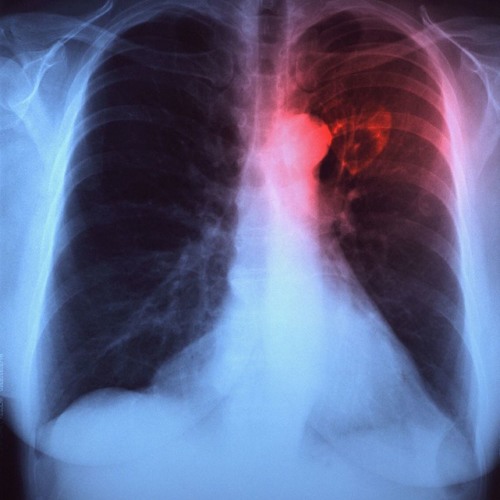

Симптомы и причины скопления воды в легких

Раздел: Ракурсы просвещения